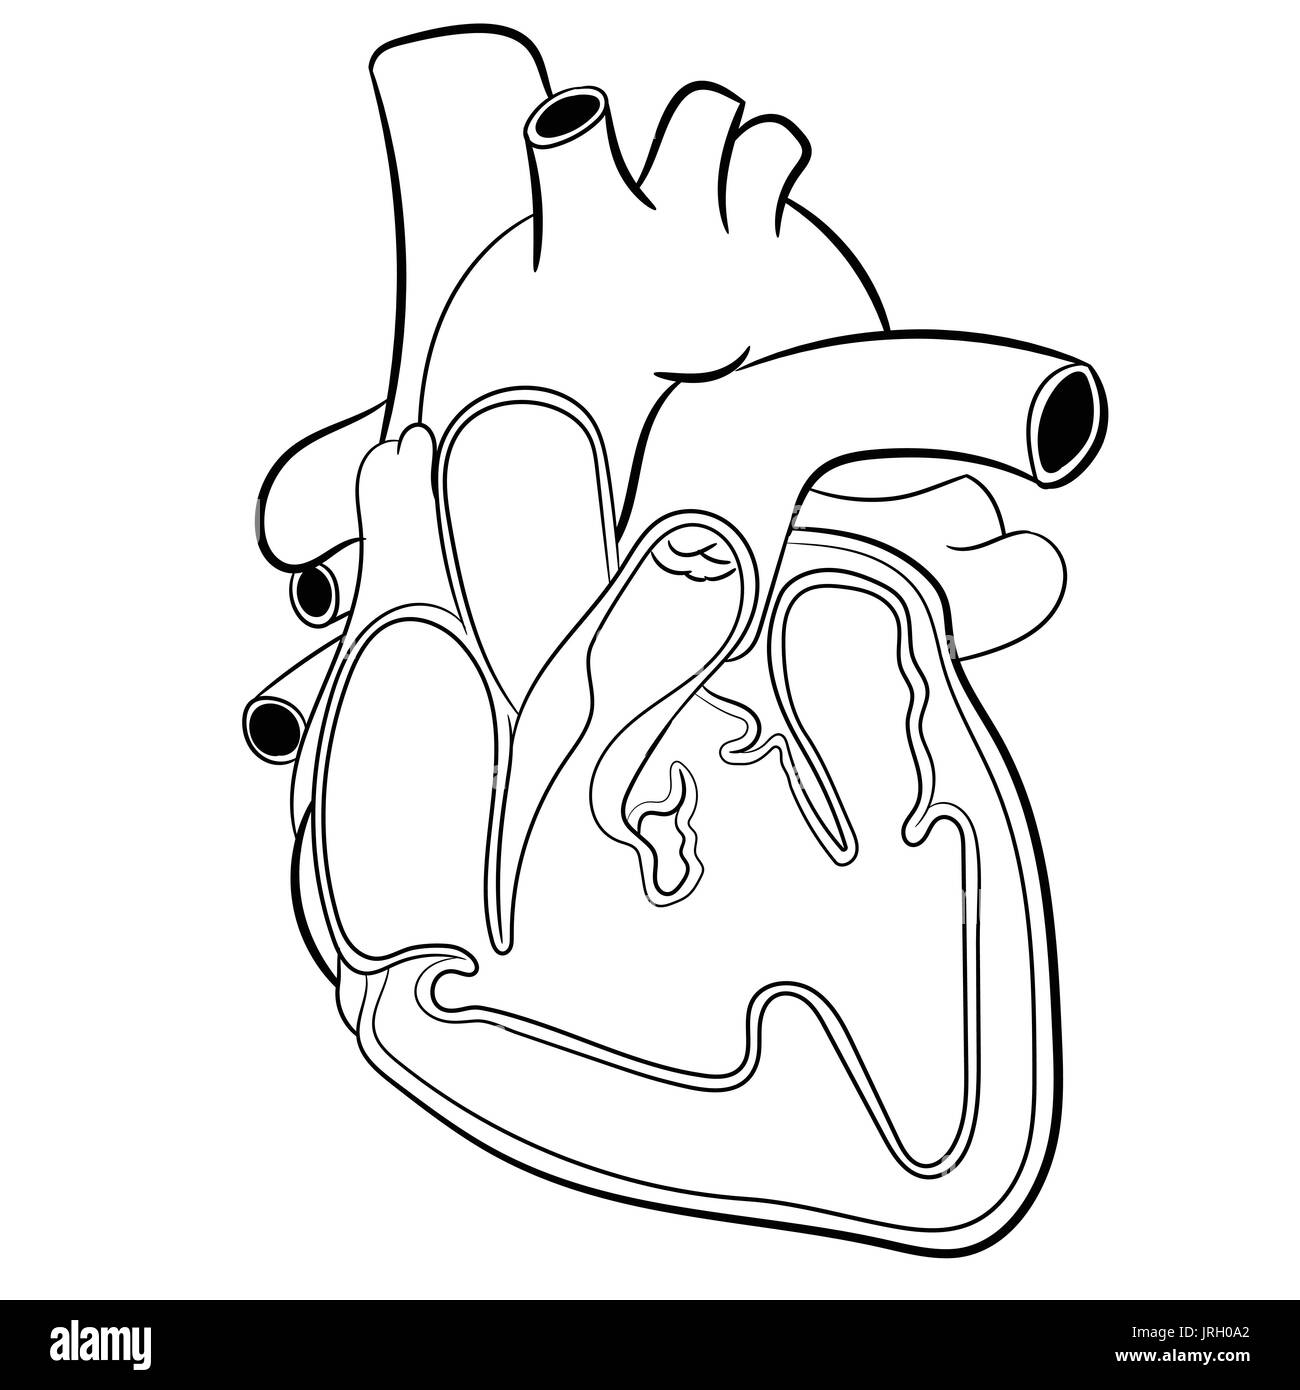

Cœur de l'homme anatomique dessiné à la main. De l'éducation médecine illustration vectorielle. Illustration de Vecteurhttps://www.alamyimages.fr/image-license-details/?v=1https://www.alamyimages.fr/coeur-de-l-homme-anatomique-dessine-a-la-main-de-l-education-medecine-illustration-vectorielle-image152193498.html

Cœur de l'homme anatomique dessiné à la main. De l'éducation médecine illustration vectorielle. Illustration de Vecteurhttps://www.alamyimages.fr/image-license-details/?v=1https://www.alamyimages.fr/coeur-de-l-homme-anatomique-dessine-a-la-main-de-l-education-medecine-illustration-vectorielle-image152193498.htmlRFJRH0A2–Cœur de l'homme anatomique dessiné à la main. De l'éducation médecine illustration vectorielle.